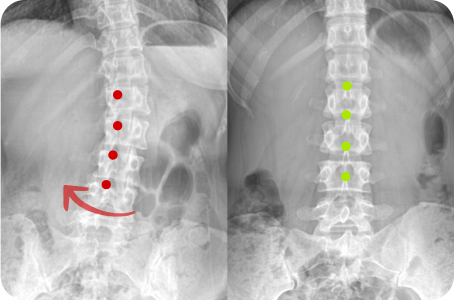

3차원 척추교정이란?

척추의 틀어진 방향과 휘어진 각도는 사람마다 모두 다릅니다.

옆, 앞, 뒤가 각자 틀어지고 꼬인 척추의 변형은 각도와 방향 모두를 고려한

3차원 척추 교정으로 바로잡아야 합니다.

정면, 측면 시각에서 틀어진 방향

척추 만곡의 각도

척추뼈 마디의 회전 변형

Before & After

해당 사진은 수정없는 실제 치료사진입니다.

환자의 치료결과는 환자의 상태, 치료방법 등에 따라 차이가 발생할 수 있습니다.